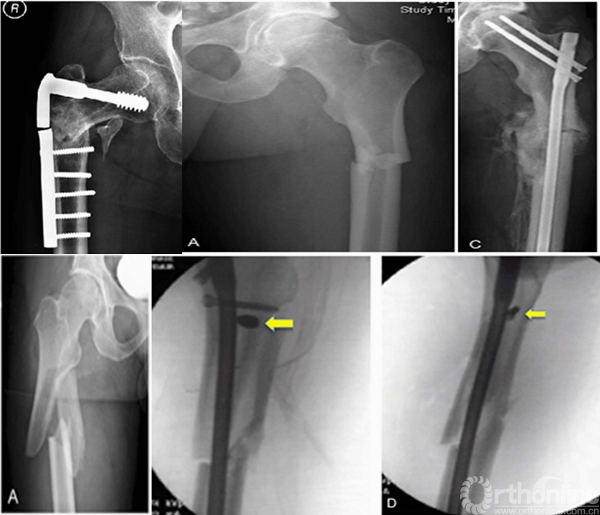

1.进针点错误导致髋内翻和固定失败;

2.辅助捆绑带或阻挡钉能增加骨折稳定性促进愈合;

3.骨折近端头颈的不稳导致髓内钉固定的失败;

4.正确的进针点和足够的髓内钉长度,即使不能达到解剖复位,也能收到满意的愈合结果;

5.内侧粉碎和钢板远端螺钉数量不足是失败原因之一;

股骨侧方钢板螺钉重建有很高的失败率,主张髓内固定IMN+适当的阻挡钉技术,可以增加髓内钉的稳定性,防止切割。

进针点和力线很难把握,即使应用很巧妙的复位技术获得了术后很好的力线,避免了髋内翻,但如此大块的骨块劈裂游离不处理,会存在退钉和骨不连或者髓内钉断裂的风险。

钱XX,女,43岁

术后